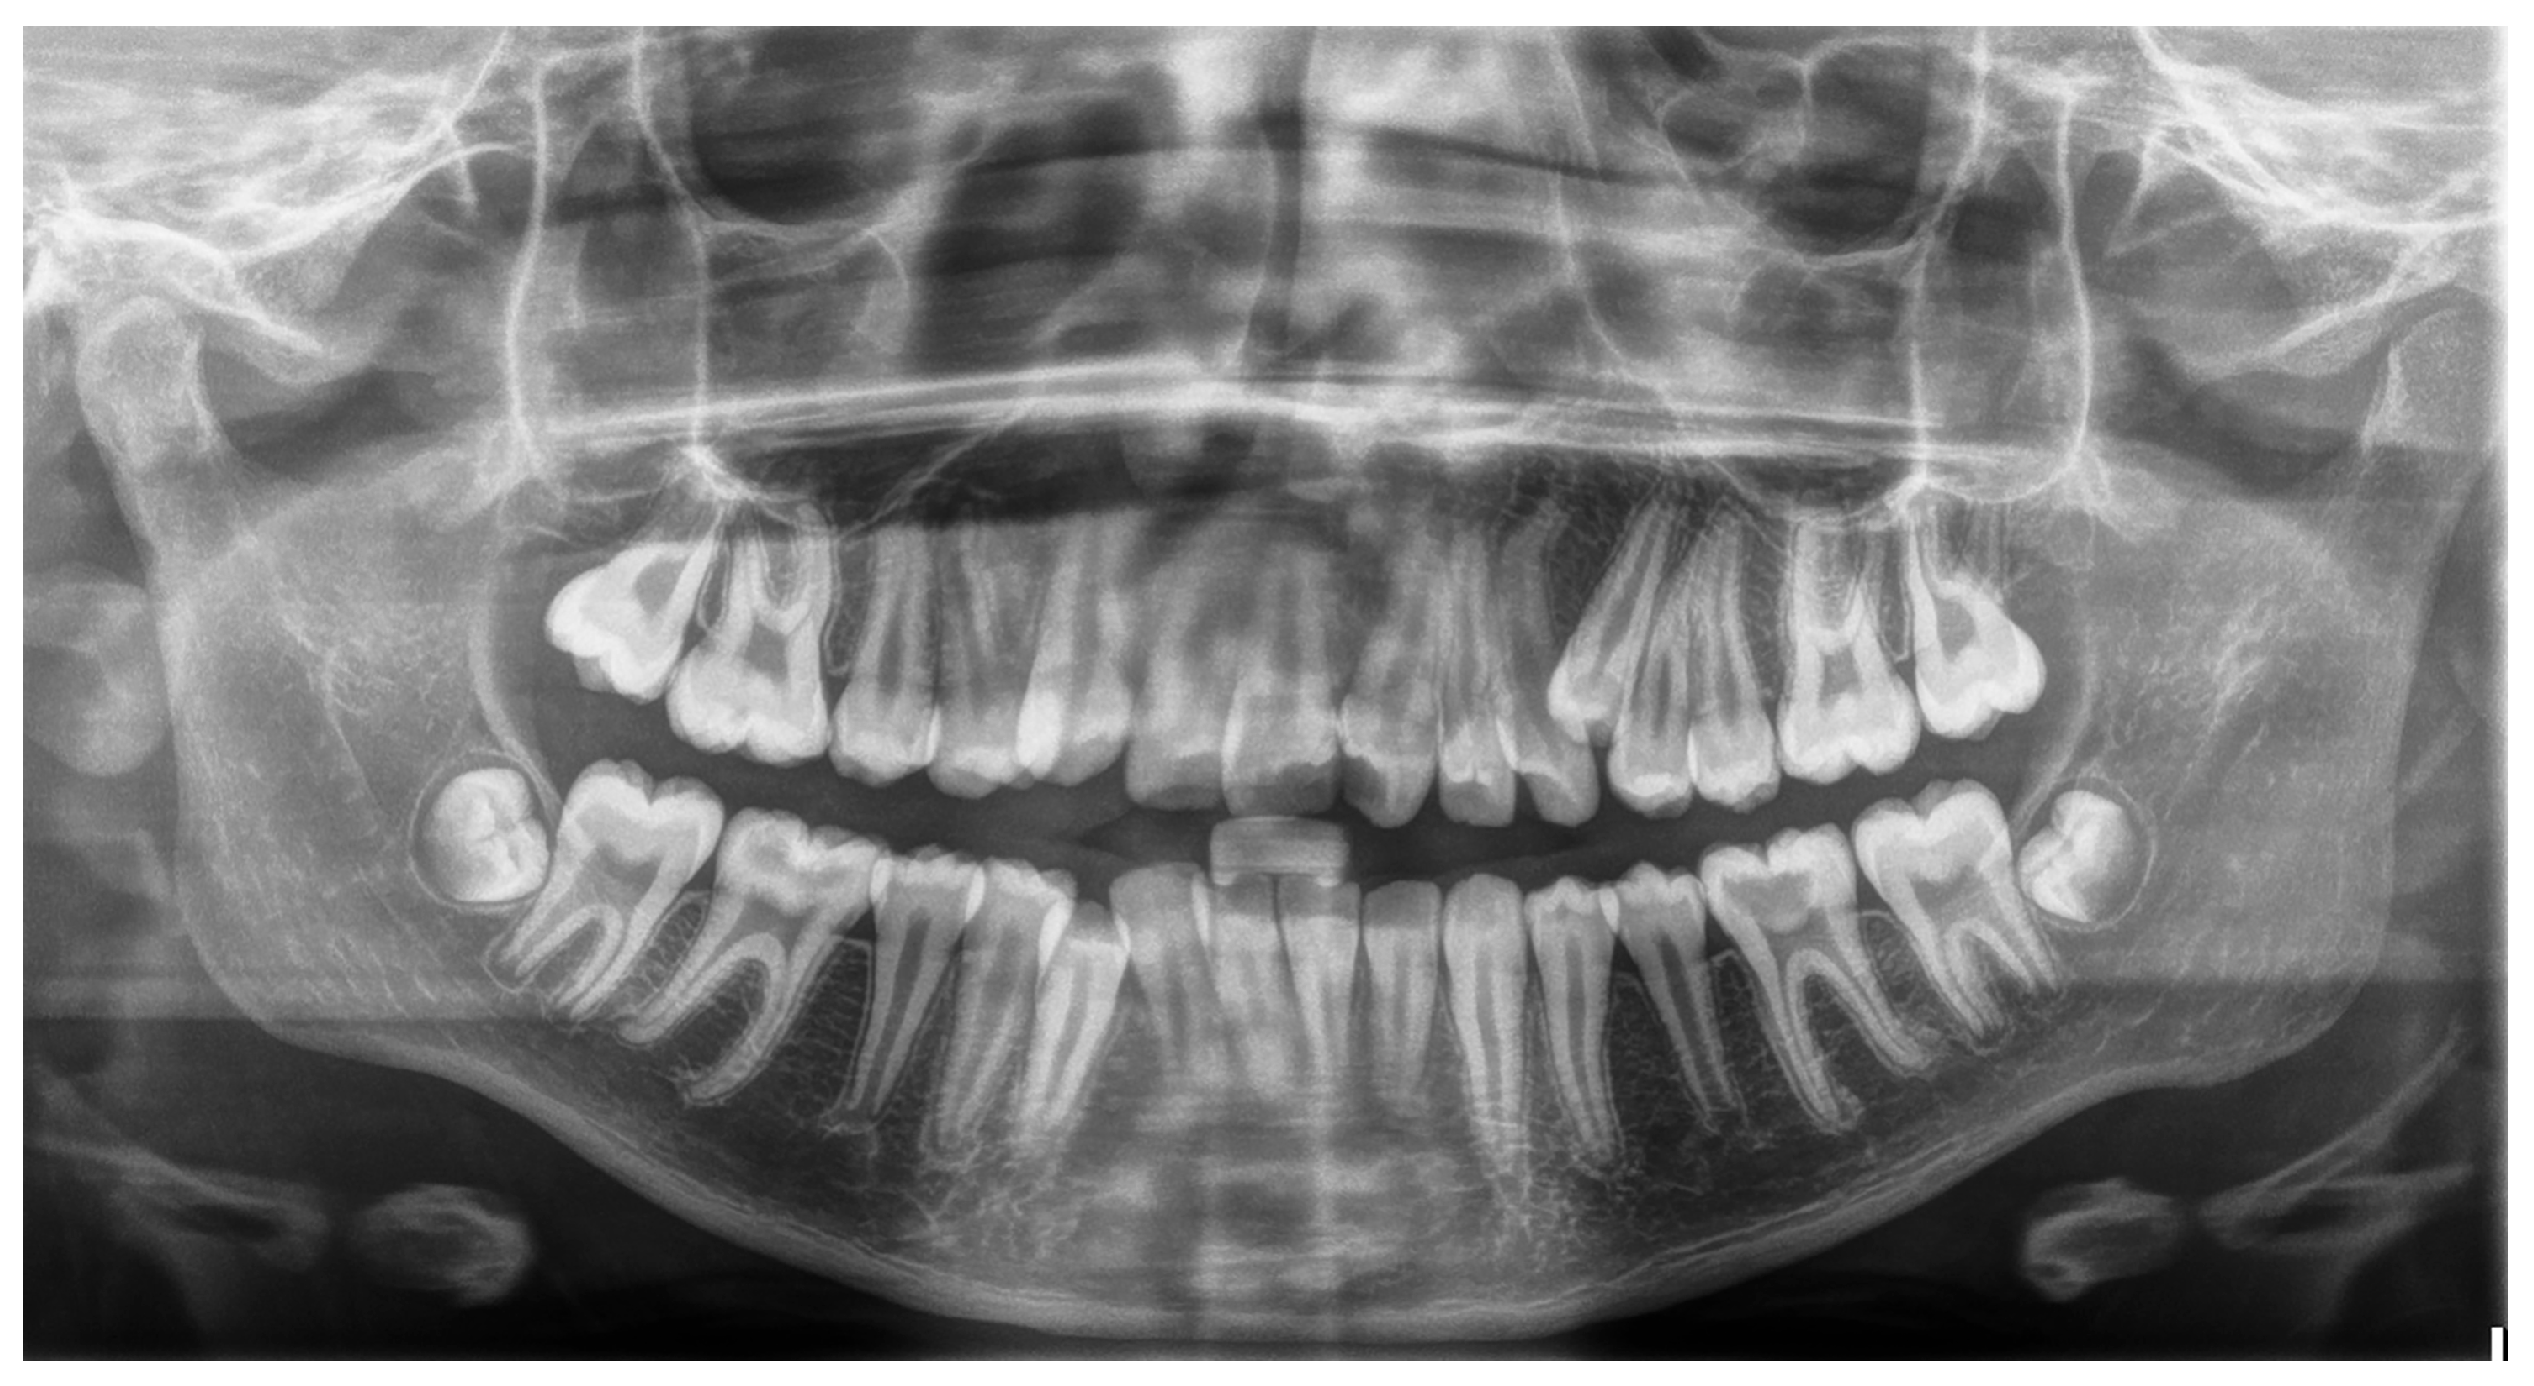

Figure 2. Panoramic radiograph of a patient with supernumerary maxillary left premolar.